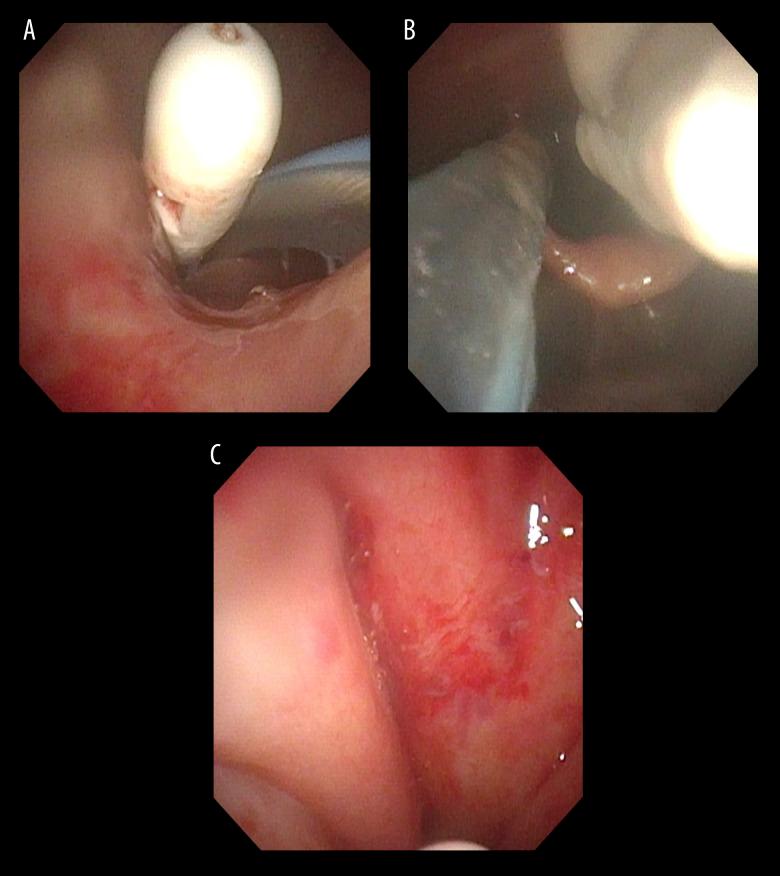

BACKGROUND The nasogastric tube (NGT) is a common medical device, and serious complications associated with NGT insertions are rare. The most common serious complication is tracheal insertion; cervical emphysema and pneumomediastinum are rare. There are several methods for confirming the location of the NGT, but a single method of confirmation is often inadequate. Confirmation by air insufflation into the NGT is currently not recommended and is highly invasive. Here, we report a case of cervical emphysema and pneumomediastinum caused by an NGT. CASE REPORT A 94-year-old woman experienced a stroke and was hospitalized for neurosurgery. The nurse inserted an NGT and performed insufflation, but air sounds were not detected. Chest radiography did not reveal the tip of the NGT. Computed tomography (CT) revealed cervical emphysema, pneumomediastinum, an NGT bent in the esophagus, and the distal end of the NGT in the nasopharynx. Nasopharyngeal endoscopy revealed damaged nasopharyngeal mucosa and the distal end of the NGT. The patient was diagnosed with insufflated air passing through the damaged nasopharynx, which had spread to the cervical area and mediastinum. The NGT was removed, and the patient was treated with antibiotics. CT showed cervical emphysema, and the pneumomediastinum resolved after 20 days. CONCLUSIONS It is important to recognize that there are numerous serious and unexpected complications associated with NGT. Different methods should be considered and used to confirm the location of an NGT. Further studies on the confirmation methods and dissemination of such knowledge are required to reduce NGT complications.

一名 94 岁女性因中风住院接受神经外科治疗。护士插入了一根 NGT 并进行了充气,但未听到空气声。胸部 X 光片未显示 NGT 的尖端。计算机断层扫描(CT)显示颈气肿、纵隔气肿、NGT 在食管中弯曲以及 NGT 的远端在鼻咽部。鼻咽喉镜检查显示鼻咽部黏膜受损和 NGT 的远端。患者被诊断为充气的空气通过受损的鼻咽部扩散到颈部和纵隔。NGT 被取出,患者接受了抗生素治疗。CT 显示颈气肿,20 天后纵隔气肿消退。